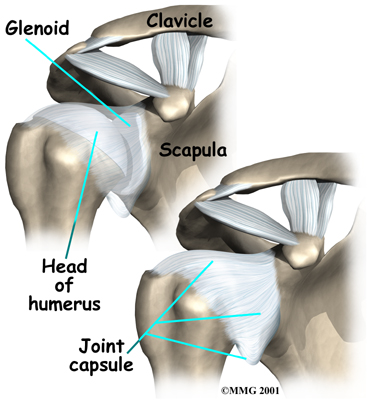

The shoulder is made up of three bones: the scapula (shoulder blade), the humerus (upper arm bone), and the clavicle (collarbone). The joint capsule is a watertight sac that encloses the joint and the fluids that bathe and lubricate it. The walls of the joint capsule are made up of ligaments. Ligaments are soft connective tissues that attach bones to bones. The joint capsule has a considerable amount of slack (loose tissue), so the shoulder is unrestricted as it moves through its large range of motion.

The shoulder is made up of three bones: the scapula (shoulder blade), the humerus (upper arm bone), and the clavicle (collarbone). The joint capsule is a watertight sac that encloses the joint and the fluids that bathe and lubricate it. The walls of the joint capsule are made up of ligaments. Ligaments are soft connective tissues that attach bones to bones. The joint capsule has a considerable amount of slack (loose tissue), so the shoulder is unrestricted as it moves through its large range of motion.

The shoulder is made up of three bones: the scapula (shoulder blade), the humerus (upper arm bone), and the clavicle (collarbone). The joint capsule is a watertight sac that encloses the joint and the fluids that bathe and lubricate it. The walls of the joint capsule are made up of ligaments. Ligaments are soft connective tissues that attach bones to bones. The joint capsule has a considerable amount of slack (loose tissue), so the shoulder is unrestricted as it moves through its large range of motion.

The shoulder is made up of three bones: the scapula (shoulder blade), the humerus (upper arm bone), and the clavicle (collarbone). The joint capsule is a watertight sac that encloses the joint and the fluids that bathe and lubricate it. The walls of the joint capsule are made up of ligaments. Ligaments are soft connective tissues that attach bones to bones. The joint capsule has a considerable amount of slack (loose tissue), so the shoulder is unrestricted as it moves through its large range of motion. As the name suggests, adhesive capsulitis affects the fibrous ligaments that surround the shoulder forming the capsule. The condition referred to as a frozen shoulder usually doesn't involve the capsule. Secondary adhesive capsulitis (or true frozen shoulder) might have some joint capsule changes but the shoulder stiffness is really coming from something other than the joint capsule. Some of the conditions associated with secondary adhesive capsulitis include rotator cuff tears, biceps tendinitis, and arthritis. In either condition, the normally loose parts of the joint capsule stick together. This seriously limits the shoulder's ability to move, and causes the shoulder to relatively freeze.